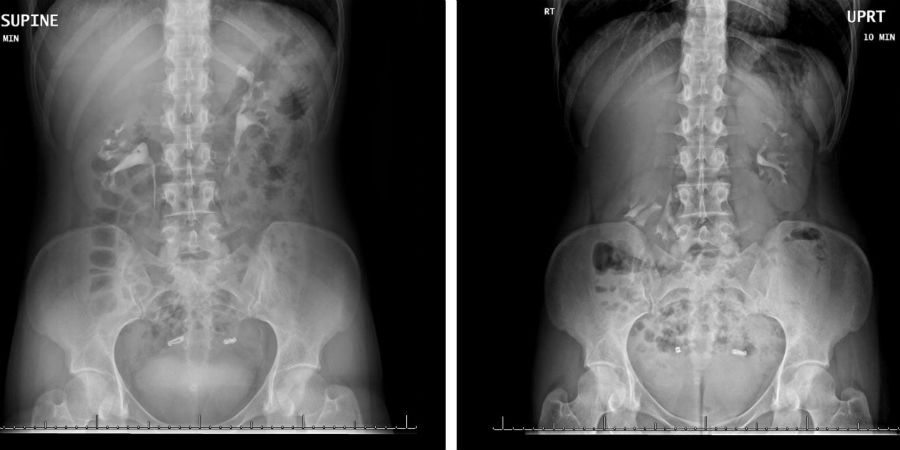

Het bleek dat de rechter nier van de vrouw zich maar liefst zes centimeter naar beneden verplaatste wanneer ze ging staan. Dit fenomeen wordt ook wel nefroptosis of ‘wandelende nier’ genoemd. In deze afbeelding zijn beide scans afgebeeld en is de rechter nier omcirkeld.

Op de linker scan lag de vrouw op haar rug en op de rechter stond ze rechtop. De rechter nier (omcirkeld in de rechter afbeelding) bevindt zich duidelijk een stuk lager dan de linker die nog netjes op zijn plek net onder de ribben zit.